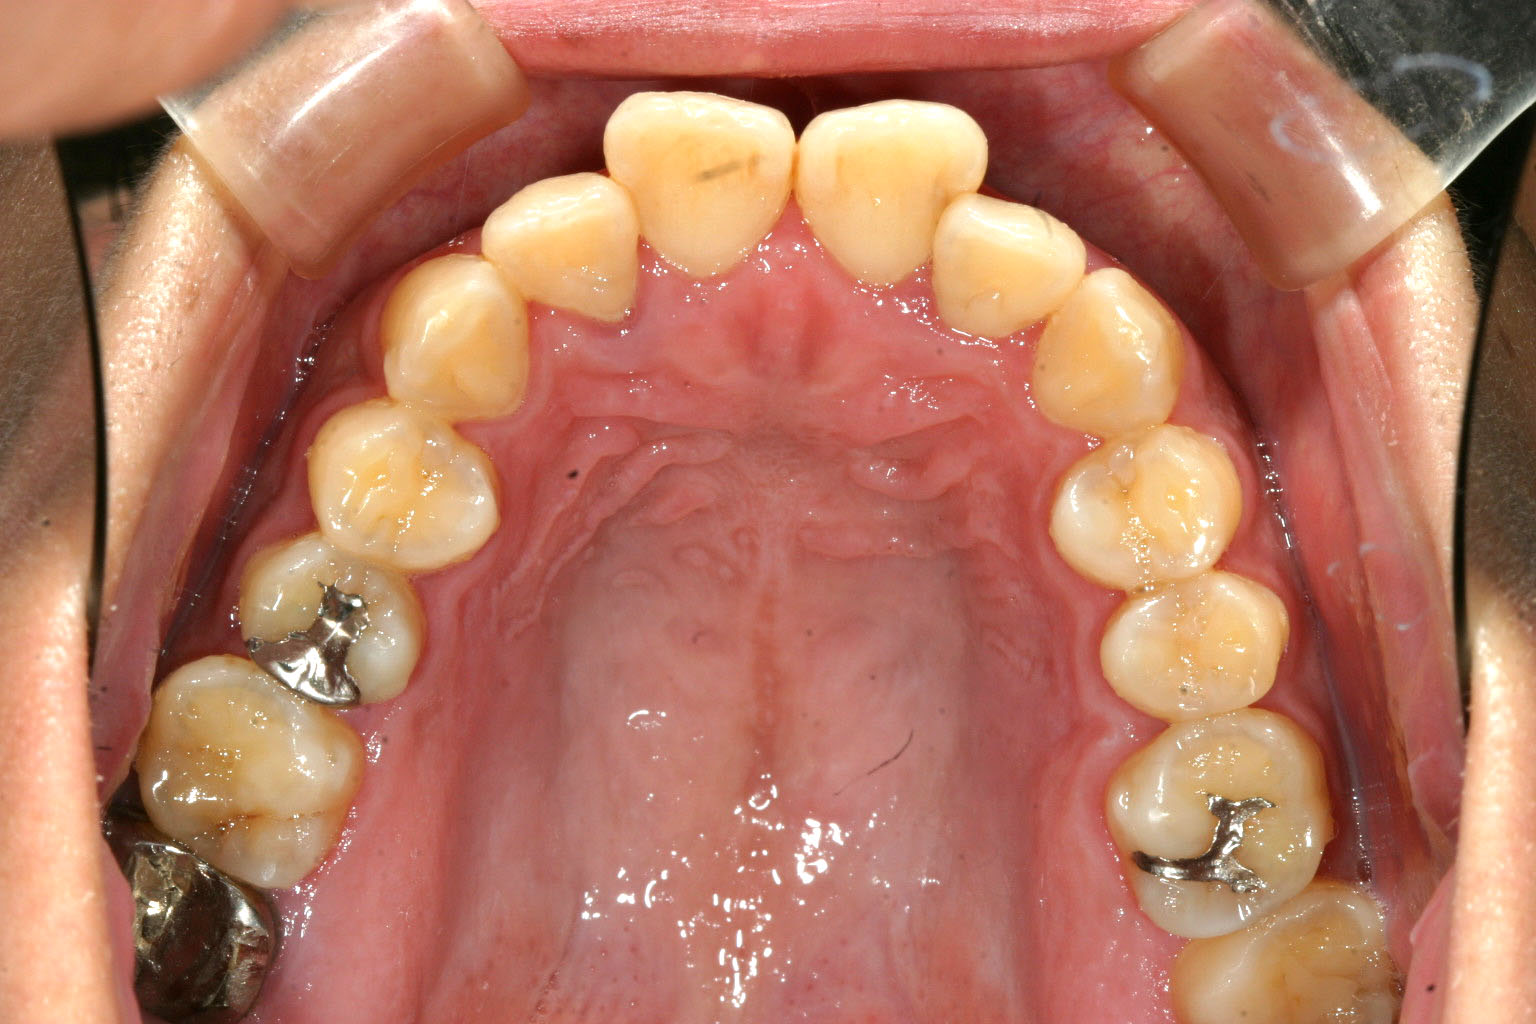

アーチが狭いお陰で前歯が前突しています。

今回は非抜歯でと希望の為何処まで入るかやってみました。